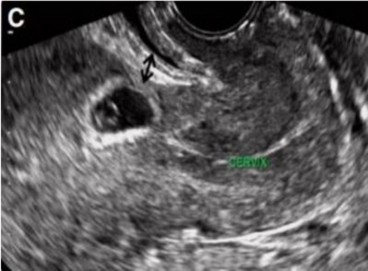

Hình 1.2. Hình ảnh túi ối ở SMLT qua siêu âm đường âm đạo [20]

Siêu âm đường âm đạo được xem là phương tiện tốt và sớm để chẩn đoán chửa SMLT [22-24]. Trên mặt cắt dọc qua tử cung có thể xác định vị trí túi ối ở đoạn eo tử cung ngang SMLT với độ nhạy 86,4 - 95%.

Tiêu chuẩn chẩn đoán chửa SMLT qua siêu âm theo RCOG 2014 gồm các triệu chứng chính là:

(1) BTC rỗng, không có túi thai trong khoang nội mạc tử cung;

(2) Túi thai hoặc khối tế bào nuôi bám vào vùng VMC ở đoạn eo tử cung;

(3) Lớp cơ tử cung giữa bàng quang và túi thai biến mất hoặc rất mỏng;

(4) Tăng sinh mạch máu quanh khối thai qua siêu âm Doppler;

(5) Kênh ống cổ tử cung trống.